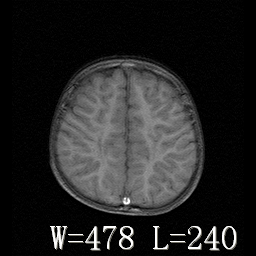

标题: PED3374:儿童脑室周围白质软化症。

男,4岁半,不能独行。

脑室周围白质明显减少,白质内见多量斑片状长t1长t2信号,脑皮质与脑室缘的距离变小,脑室还是有扩大,且局部脑室缘不规整。结合患者症状支持室旁脑白质软化症,问一下病史看有没有hie史等